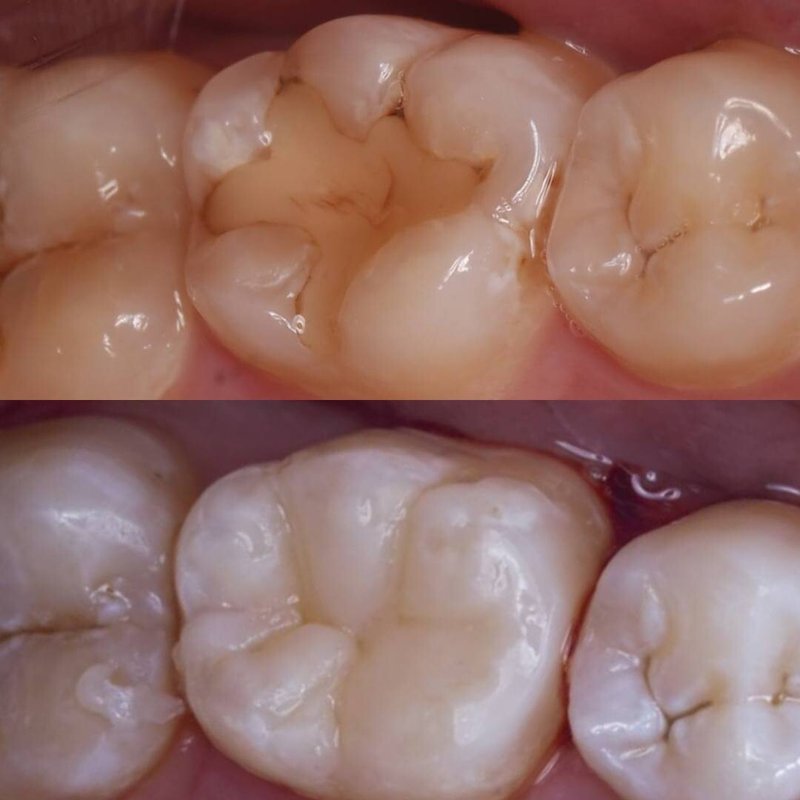

Фотогалерея